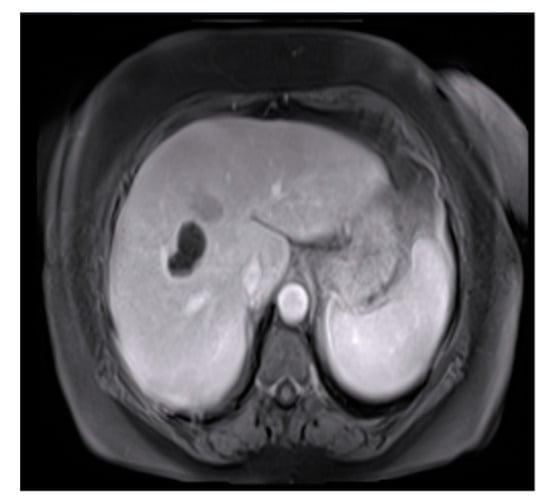

Figure 3.

Original image.